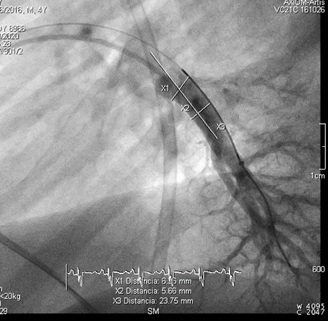

Catheterization was naturally indicated for managing his condition. We first performed an ultrasonic evaluation of his femoral veins to ensure they had at least a 3 mm axial diameter. After securing vascular access, angiographic verification of the right femoral vein patency and diameter was performed. We conducted a standard diagnostic hemodynamic catheterization under fluoroscopic control in a biplane system (Artis Zee, Siemens®) with a low dose protocol. Then, pump injection with diluted contrast (0.5 ml of isosmolar contrast per kg of body weight, diluted with isotonic saline solution in a 70% contrast to 30% saline ratio) into the left pulmonary artery was achieved with biplanar acquisition at 15 images per second (Figures 1 & 2). This process was to examine the left lung pulmonary arterial architecture to find an ideal implantation site, requiring a length of at least 30 mm with initial and final diameters of 7 and 5 mm, respectively, and a bifurcation pattern showing branches larger than 3 mm in diameter. Once the target site was selected, the angiographic catheter was exchanged over a conventional 0.035 guidewire, which served as a support for successive dilations of the venous access point until the 12 F introducer advanced without resistance. A multipurpose 5F catheter was then advanced over the guidewire, followed by a 0.35 hydrophilic guidewire to position the catheter in the selected segment. After removing the hydrophilic guidewire, a small manual contrast injection was performed to evaluate the distal anatomy before advancing a 0.018” guidewire through the catheter, ensuring the floppy segment did not distort or angle and that a non-floppy portion was present at the device implantation site. With these considerations meticulously observed, and the catheter removed, the catheter housing the CardioMEMS was advanced, ensuring smooth and natural progression until reaching the destination and proceeding with its release. Following this, the catheter was removed, and the previous multipurpose catheter was reinserted to a position proximal to the device's release point. A manual contrast injection was then performed through the catheter via a Y-connector without removing the guidewire, and biplanar images were acquired to assess the occupied volume of the device, its loops, and any potential interference with the distal filling of that branch or collateral vessels. High-quality pulmonary pressures were obtained through CardioMEMS®, so the procedure was concluded without any problems related to the device or vascular access. Successful monitoring of the pulmonary pressures facilitated the management of this challenging patient, and a heart transplant was successfully performed 13 months later. The surgery required extensive manipulation of the patient's thorax, which, as evidenced in radiographs taken in the following days, led to displacement of the device that did not interfere with measurements. The patient underwent subsequent catheterizations for post-transplant protocolized control without complications in vascular access, performed through the same right femoral vein. On two occasions, an excellent correlation was observed between the invasive measurements of pulmonary pressures and the results from the CardioMEMS check. During a recent catheterization, within the regular control indications with the patient weighing 28 kg, this correlation was confirmed, and an angiography was performed on the left pulmonary branch showing the arterial vascular architecture (Figures 3 & 4). Despite the displaced device, there is no interference or obstruction to the permeability of the lobar and sub segmental branches in angiography nor in pressures distal or proximal and an excellent correlation was obtained between invasive (Figure 5) and CardioMEMS® measurements (Figure 6). The procedure confirmed the permeability of the pulmonary branches, reaffirming the utility of the device for continuous and non-invasive monitoring in a pediatric context.

Figure 4: Lateral angiography of left inferior lobar pulmonary artery 4 years post-CardioMEMS® Implantation.